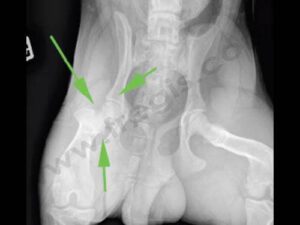

Nécrose aseptique de la tête fémorale

Chien atteint d’une nécrose aseptique de la tête fémorale gauche (articulation de la hanche) (flèche). Radiographie avant la chirurgie